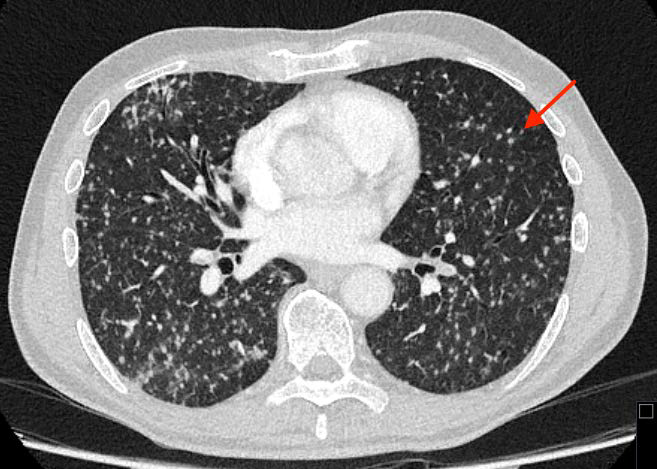

Disseminated Miliary Tuberculosis Following Intravesical BCG Therapy: A Rare But Serious Complication

Al-Taiee Baker, Mejdoubi Lamiss, Slavicek Jakob, Hergan Klaus, Zandieh Shahin

1-8